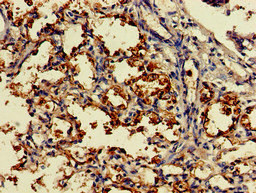

Immunohistochemistry of paraffin-embedded human lung tissue using CSB-PA006593LA01HU at dilution of 1:100